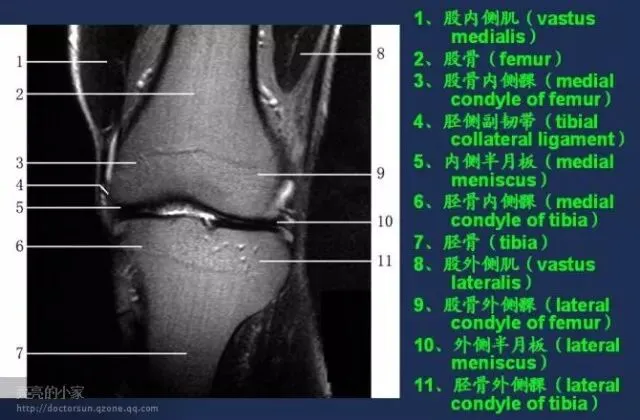

收藏!全身MRI解剖图谱,医生必备